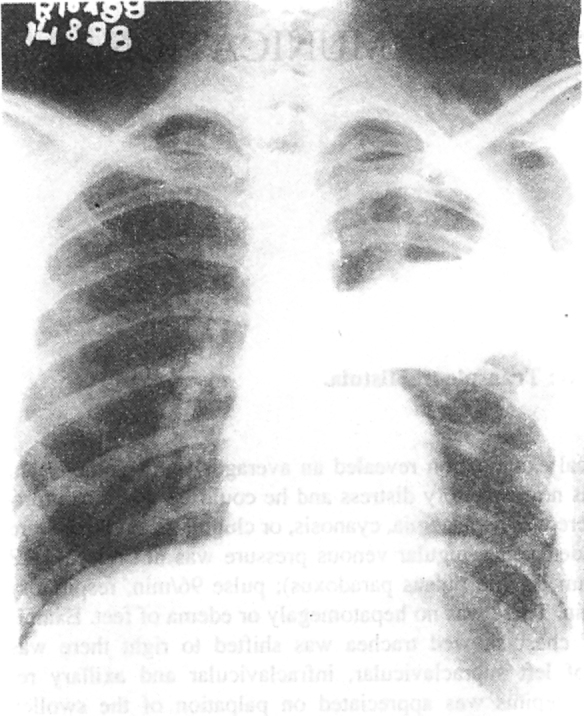

Investigations revealed a haemoglobin value of 9.1 gm/dl, a total leukocyte count of 16,400/cmm with polymorphonuclear leukocytosis (P-84%, L-12%, E-3%, and M-1%), and an erythrocyte sedimentation rate of 58mm/h (Wintrobe). Serum biochemistry values were normal. The chest radiograph showed a thick walled cavitary lesion in left upper and mid zones with a horizontal fluid level extending outside the bony cage and presence of air in soft tissues (Fig 1). The left costophrenic angle was not obliterated. The lateral radiograph showed dual air fluid level in the region of anterior segment of left upper lobe. A CT scan of chest revealed thick irregular walled cavitary lesion in anterior segment of left upper lobe extending and communicating with a chest wall abscess (Fig 2). Ultrasonography revealed an intrapulmonary well defined echogenic collection, which also contained air. In addition there was to and fro movement of air between chest wall abscess and lung abscess best appreciated during respiration and with probe pressure. Pleural collection was not appreciated. Sputum Gram stain revealed Gram positive cocci in short chains and bunches. Sputum smear was negative for acid fast bacilli and fungi. Culture of sputum grew Staphylococcus aureus. Needle aspirate of chest wall abscess also grew Staphylococcus aureus.

Fig. 1.

The chest radiograph posteroanterior view showing a thick walled cavitary lesion in left upper and mid zones with a horizontal fluid level extending outside the bony cage. An air fluid level is present in soft tissues. The left costophrenic angle is not obliterated